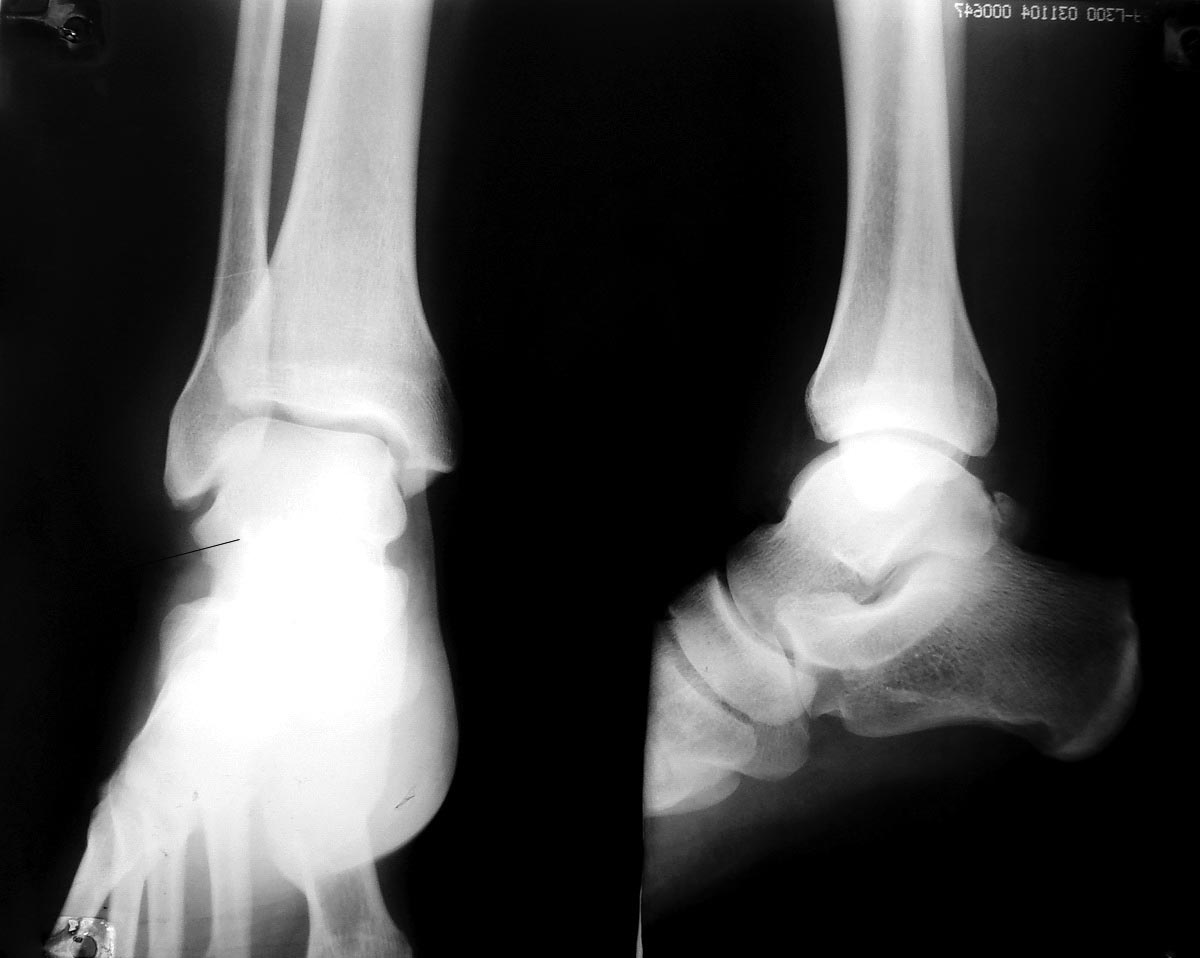

Обратился больной 36 лет, мужчина. Оступился на паребрике. Беспокоит боль в области голеностопного сустава, хромота. По рентгенограмме - перелом одного из бугорков. То, что латеральный выявлено в ходе выполненного КТ (к сожалению, визуальных результатов на руках нет). На сравнительной рентгенограмме неповрежденной стопы "os trigonum" не выявлено. В нашем учреждении мнения разделились: одни выступают за консервативное лечение, другие - за оперативное (удаление, если нет возможности фиксировать винтом типа Герберта)...

На снимках ничего не видно.

На этих снимках видно только os trigonum, которая может дебютировать болезненностью после травмы. Сейчас покой, обувь с каблуком 4-5 см.

Вообще то похоже на перелом. Было бы неплохо увидеть и здоровую стопу и КТ. Если это перелом, то остеосинтез, при такой большой площади контакта отломков, может оказаться менее травматичной и не более сложной, чем удаление бугорка, операцией.